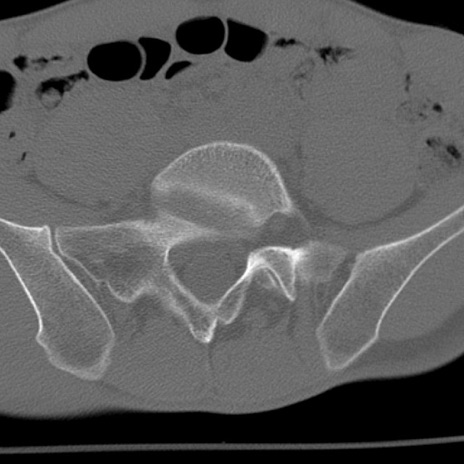

症例3 腰椎CT(横断像)

腰椎CT